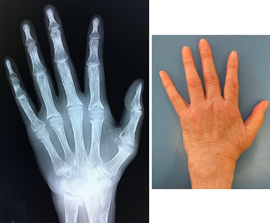

関節リウマチ

リウマチによる手・肘の変形に対する治療は一般的に難易度が高く、また習熟している施設は限られています。当院ではリウマチ手指や肘に対する人工関節手術を積極的に行い、良好な治療成績を得ています。また比較的若年の方で関節面が保たれている場合は可能な限り関節温存手術を行います。当院の担当医はリウマチ指の人工関節手術、人工肘関節手術、人工関節を用いない手指軟部組織形成術や肘関節形成術の経験も豊富です。